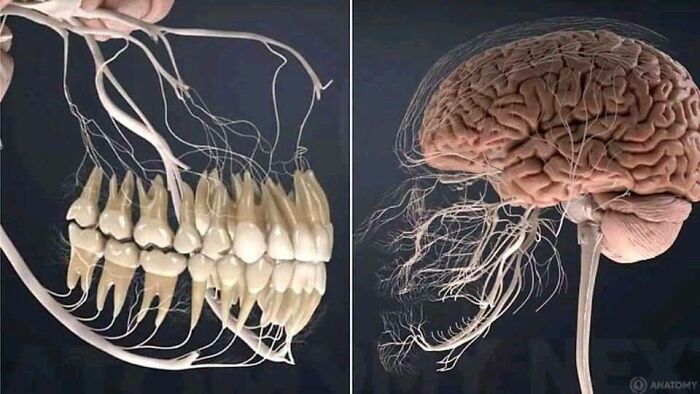

This Is What The Nerves Related To The Teeth Look Like